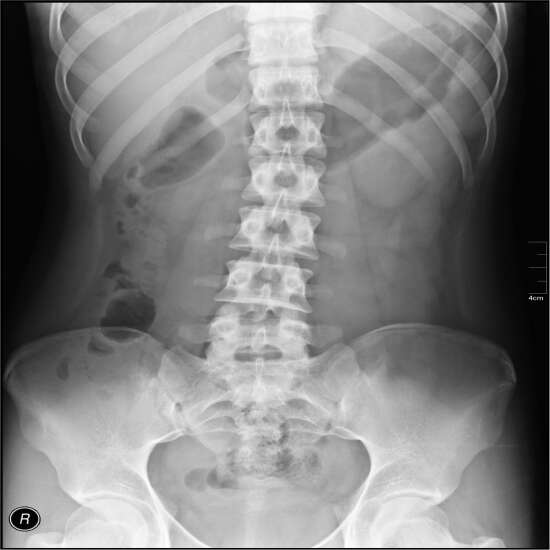

The abdomen X-ray also referred to as the KUB X-ray, is the abdomen's standing anteroposterior (AP) view. This is because the radiograph depicts the entire urinary tract, including the kidneys, ureters, and bladder. It is feasible to acquire an X-ray of the abdominal region when the patient is supine or while they are standing.

The doctor will likely order this test to diagnose the source of any stomach (abdominal) pain, check for any evidence of intestinal obstruction, and check for any gallstones or kidney stones that may be present.